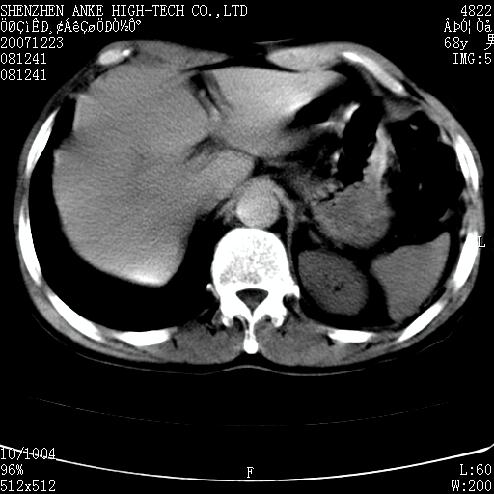

患者:男,63岁,2年前胆囊切除术后,现右上腹部剧烈疼痛近2天.

有无外伤史?右肾包膜下血肿可疑。

主要是问右肾有没有问题?患者无明显外伤史.

未见异常,病人差闭气,伪影较多.

肠道准备不好,干扰影大。

肠道气体伪影干扰太大了,应该是干扰所致,未见明显异常。

肠道准备不好,胃底后壁显示不清,右肾改变考虑为伪影。